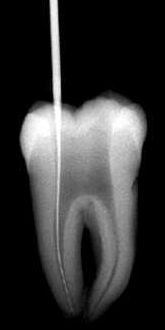

Se debe rectificar la cámara para que la lima acceda en forma vertical "A" para ello se utiliza la fresa SX  ó Pre RaCe

Acceso vertical con lima 10 manual